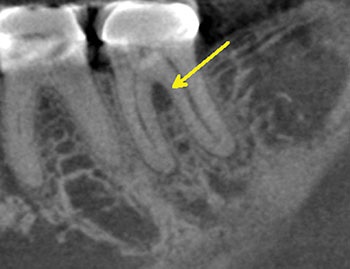

Case 1:A J-shaped lesion

Tooth #30 had a diagnosis of previous root canal treatment with symptomatic apical periodontitis. The mesial root had a classic J-shaped radiographic lesion and a narrow probing defect from the buccal furcation to the root apex. No crack could be seen on what little root surface was visible. The likelihood of VRF, or the possibility of a failing root canal with a chronic apical abscess, were discussed. The latter could be treatable. The plan was to attempt re-treatment after internal inspection for a possible VRF.

Fig. 1: Preoperative PA.